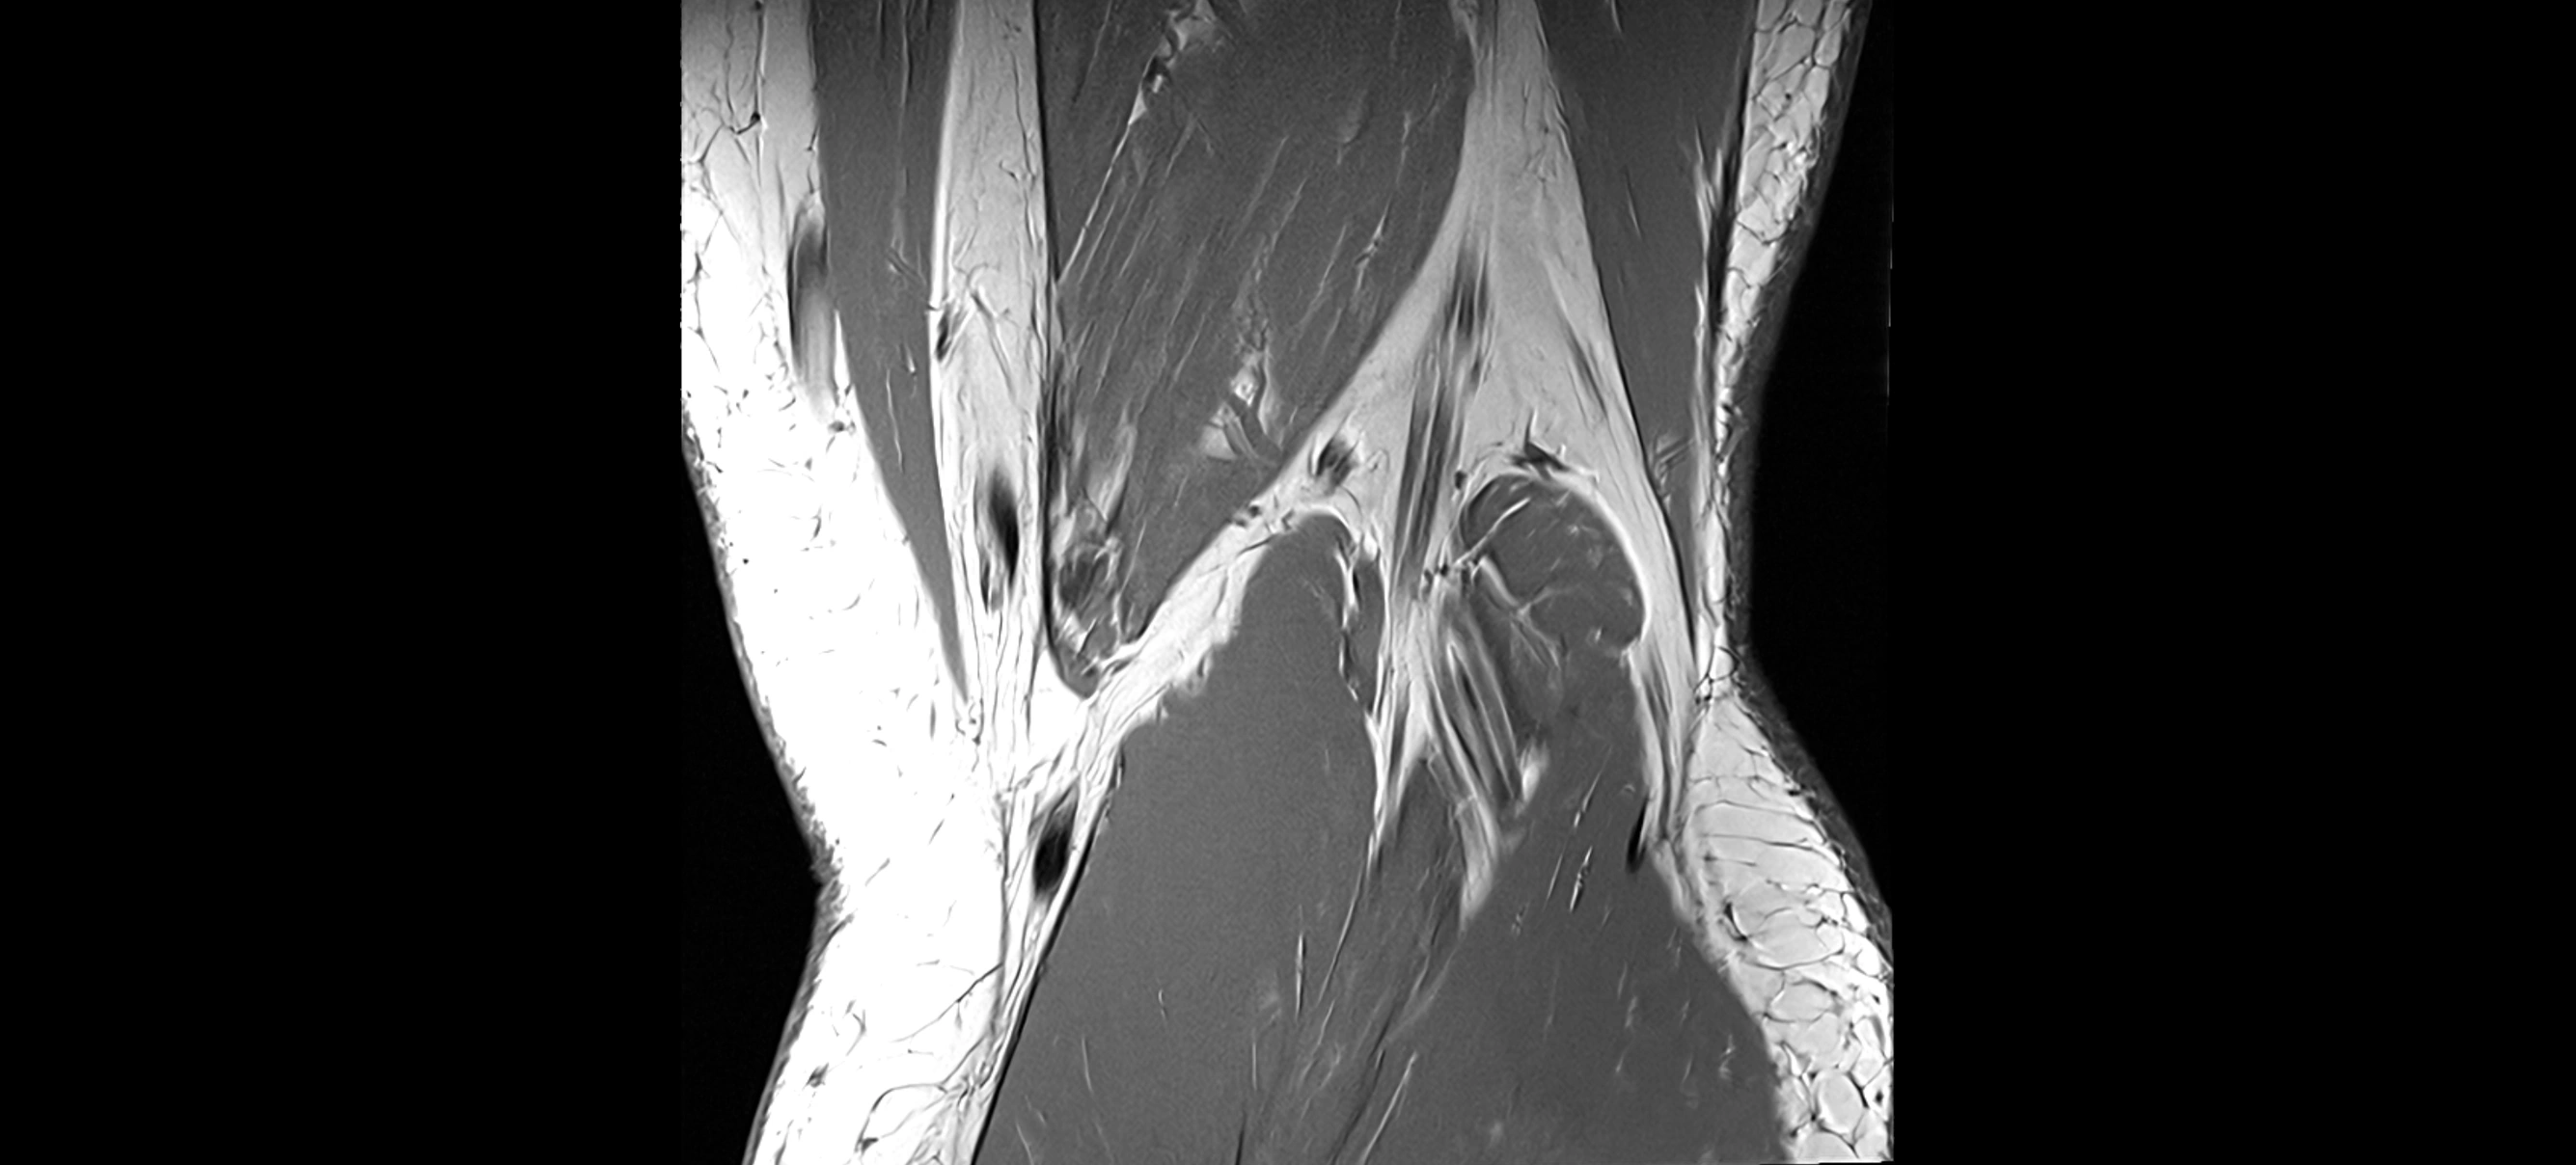

MRI images

image